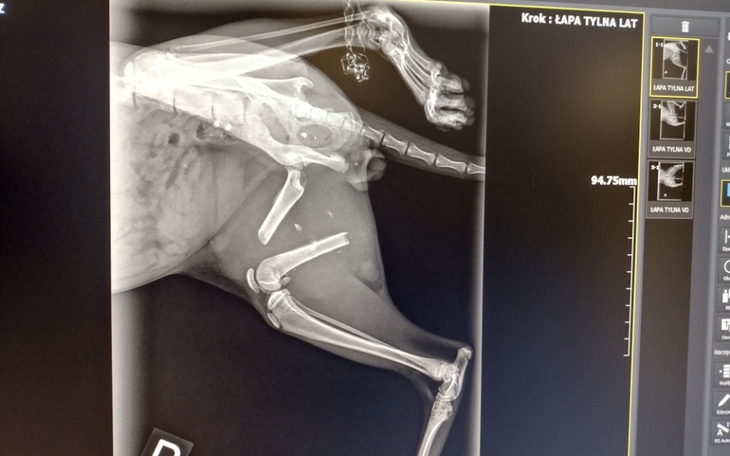

Operacja Puszka aby zespolić kości w nóżce została opłacona.

To ciężka operacja, ale udało się wydostać kość, przesuniętą i wrośniętą już w nowy mięsień ❗

Żadne ścięgno nie ucierpiało i żaden nerw😻, nóżka działa, maluch, który nasiedział się w klatce, biega na czterech łapkach, że trudno dogonić 🥰

Teraz czeka go usunięcie druta i kastracja.